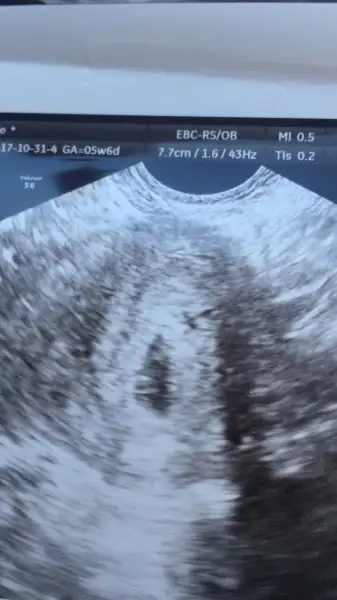

Kizlar 7+5 kalp atislarimizi duyduk sizce sag tarafta mi solda mi oluo bebis

• IMG_20171031_132735.webp

IMG_20171031_132735.webp

23,2 KB · Görüntüleme: 101

Gözünüz aydın ,Allah daim etsin kalp atışlarını inşallah. Karından baktiysa kesenin sağında görünüyor. Vajinal baktığında tam tersi oluyormuş :)